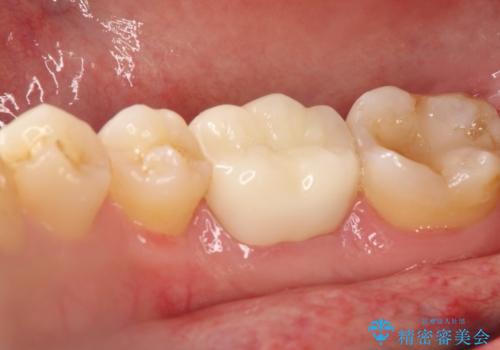

やはり内部では少量の虫歯がありましたので、拡大鏡使用して虫歯を除去しました。

虫歯の取り残した場合は将来的に再治療が高い確率で必要となります。

今回精度の高い治療を行うことで、再治療の可能性を限りになく小さくできました。